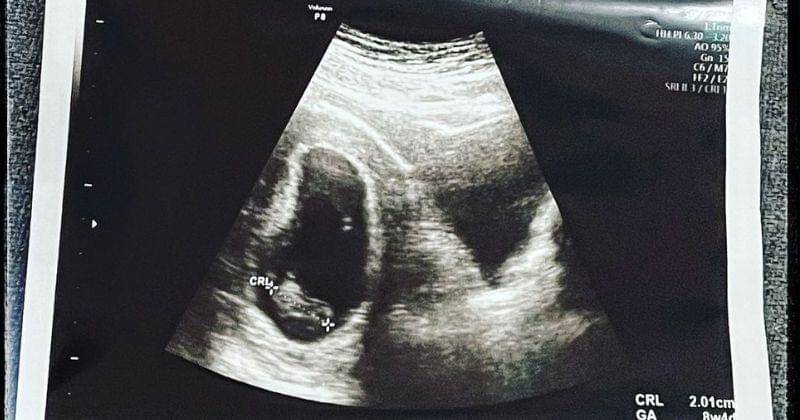

"Di usiamu yang ke 8 minggu, yang seharusnya detak dan gerakmu sudah bisa dideteksi melalui usg, ini malah sunyii, hanya ada bentukmu tanpa adanya suara apapun," tulis Via pada caption.

Pada tanggal 7 Oktober 2022, Via Vallen secara tiba-tiba mengunggah sebuah foto ultrasound kehamilannya. Sayangnya, bukan kabar bahagia melainkan kabar dukacita yang ia bagikan pada akun media sosial pribadinya itu.

Via menuliskan betapa sedihnya ia harus kehilangan janin yang ia kandung dalam usia delapan minggu tersebut.

Menurut Via, hilangnya detak jantung dan juga gerakan janin menjadi penyebab utama janinnya tak lagi berkembang. Via bahkan sempat berharap kalau janinnya bisa kembali berkembang setelah beberapa hari.

"Anakku, dokter sudah menyarankan ami untuk melepas kamu, tapi ami ga mau! Ami masih berharap nanti detak jantungmu terdeteksi, kamu gerak dan bisa berkembang lagi. Tapi sampe di hari ke 7 ini, ami udah coba USG fetomaternal. Dan hasilnya sama, rahim amii masih sunyi. Maafin ami nakk, ami mau nunggu kamu. Tapi ami ga tau berapa lama lagi ami masih dibolehin untuk nunggu kamu. Ami belum puas sama jawaban dari beberapa dokter yang ami datengin," jelas Via.